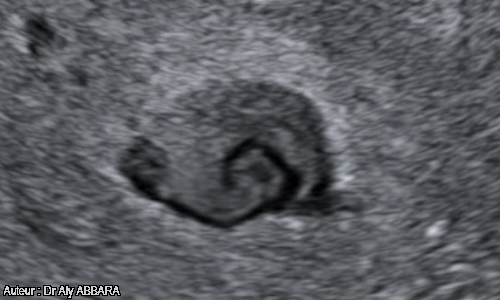

Caverne placentaire : aspect échographique sans Doppler couleur - tourbillons sanguins

• Il s'agit d'un lac intraplacentaire siégeant au centre d'un cotylédon et prenant la forme d'une lacune hétéroéchogène à contours irréguliers et un peu flous ; le contenu est animé par des flux sanguins lents et tourbillonnants accélérés par des jets artériels provenant de la circulation maternels vers les chambres intervillositaires.

• L'étude de ces flux permet l'obtention d'un signal Doppler continu tourbillonnant par l'éjection du sang maternel, à certains points périphériques, vers la cavité de cette caverne placentaire (comme dans la chambre cylindrique d'un moteur).

• Il s'agit d'une zone de régression villositaire localisée, intraplacentaire.

• A ne pas confondre avec l'hématome rétroplacentaire central.

• Les images publiées dans cette page ont été réalisées chez une femme enceinte de 37,3 semaines d'aménorrhée.